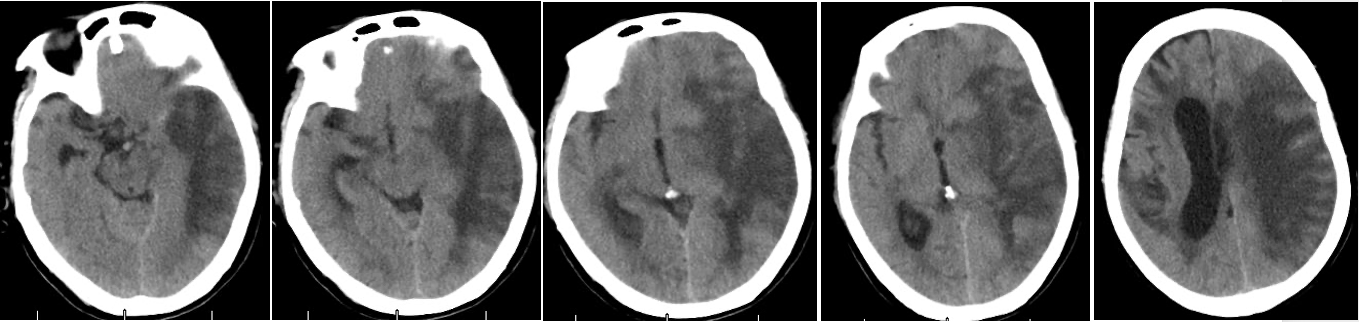

头MR回报(2025-1-13 影像序列上图已标注):左侧大脑半球急性脑梗塞,基底节区T1高信号,建议CT检查除外出血;左侧侧脑室受压变窄,中线结构右偏;颅内多发梗塞灶,部分软化灶形成;双侧脑白质缺血脱髓鞘改变。左侧大脑中动脉闭塞;双侧大脑前动脉、右侧大脑中动脉、双侧大脑后动脉多发狭窄。

头CT(2025-1-18):左侧大脑半球脑梗死;左侧侧脑室受压,中线结构稍右侧移位;颅内多发脑梗死、缺血灶,部分软化灶。三、临床印象